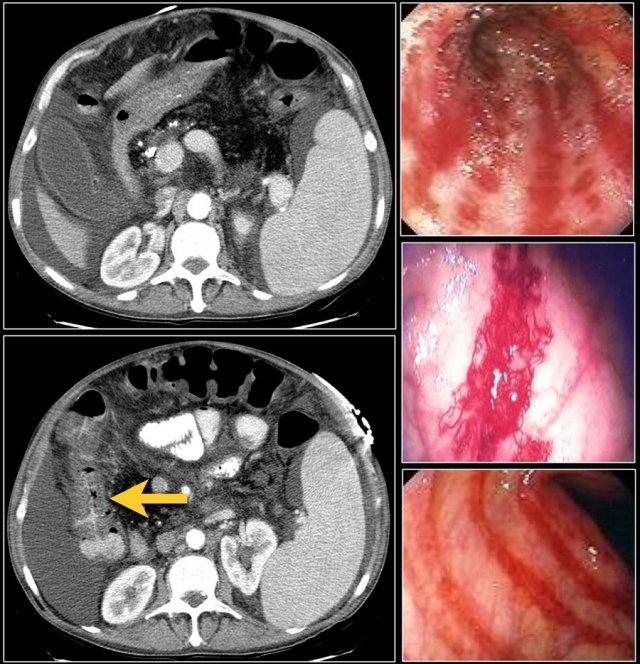

Đây là hình ảnh bệnh nhân thiếu máu cục bộ ruột do huyết khối tĩnh mạch mạc treo tràng trên – SMV (mũi tên đỏ).

Lưu ý tình trạng ứ máu tĩnh mạch trong mạc treo ruột (mũi tên vàng).